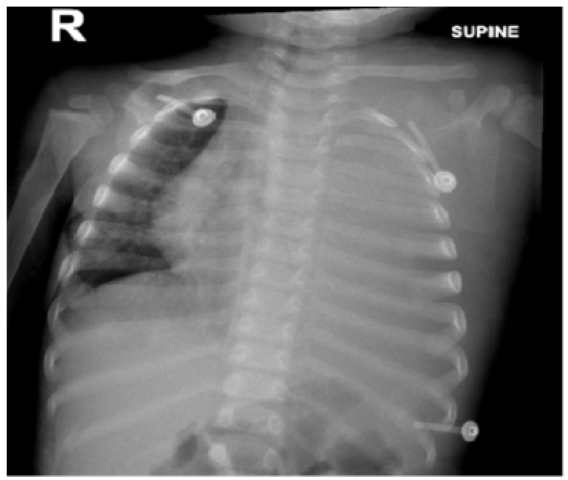

Empyema Necessitans Secondary to Methicillin Resistant Staphylococcus aureus, a Rare Complication of Empyema

Ayaz Ur Rehman, Rozina Iqbal, Ariba Siddiqui, Salman Khan, Waris Ahmad and Naveed Ur Rehman Siddiqui. 12(4): 41-46.